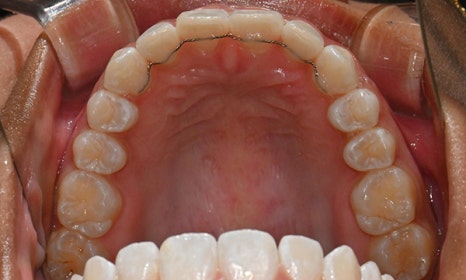

위아래 앞니 사이가 벌어져서 공간이 있었고, 앞니에 약간씩 배열이 틀어진 덧니가 있었습니다. 정면에서 보았을 때 윗니와 아래 앞니가 깊게 물려서 아래 앞니가 잘 보이지 않는 과개교합 양상을 보이고 있었습니다. 또한 왼쪽 아래 작은 어금니가 90도 앞으로 돌아가서 좌측 치아 배열 및 교합이 좋지 않은 상태였습니다.

초진시 구내사진 (2025. 3.31)